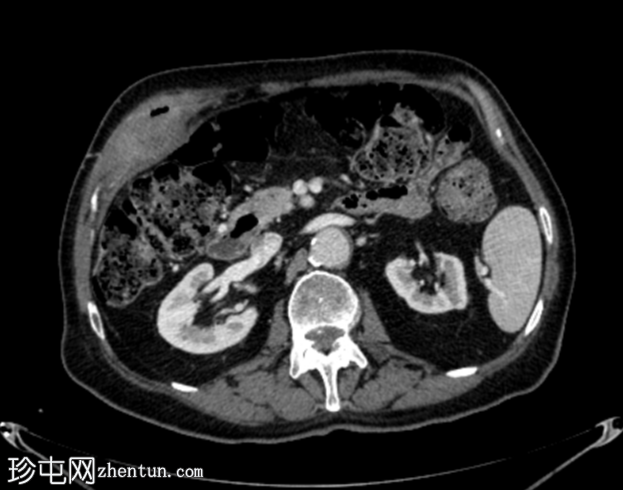

4.png

轴位增强扫描

门静脉期

胆囊底部可见一枚较大的(3厘米)高密度结石,胆囊壁增厚并强化,主要位于胆囊底部。胆囊壁可见一小穿孔,感染扩散至胆囊外,并在肝下区可见气体腔。感染进一步扩散至腹壁肌肉,腹壁肌肉内可见脓肿,边缘强化明显,囊性坏死中心,腔内可见气体腔。十二指肠第一段与炎症胆囊粘连。

检查结果提示急性胆囊炎合并腹壁脓肿。

患者接受了紧急手术,术中发现急性胆囊炎,并发胆囊壁穿孔、胆囊十二指肠瘘和前腹壁脓肿形成。